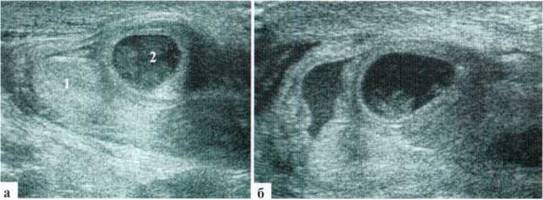

У детей раннего возраста изменения придатка бывают выражены еще более резко, по размерам он может приближаться к размерам яичка, форма его чаще становится неправильной. Всегда имеет место резкое усиление сосудистого рисунка (рис. 2.2.3).

Рис. 2.2.3. Эпидидимиту младенца. Придаток (2) по размерам практически одинаковый с яичком (I), резко гиперемирован